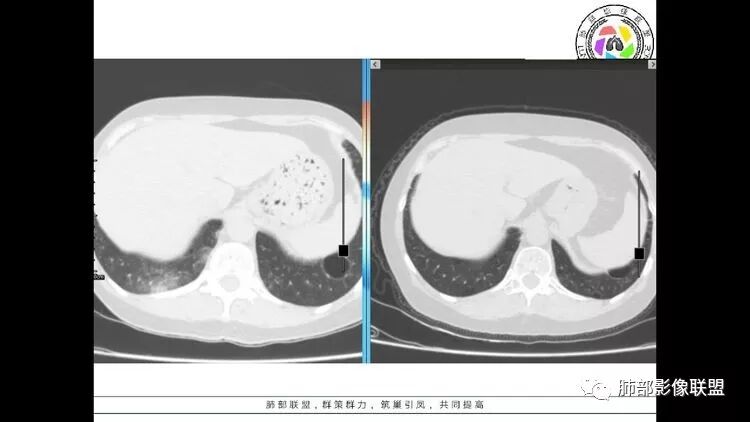

wonderful

多发气囊,气囊内可见血管进入,因患者眼干伴类风湿,可能有干燥综合征,那LIP可能性大。因为不是育龄期发病,可排除LAM。患者左纵膈淋巴结肿大,且有融合趋势,结合左下肺病灶,考虑合并恶性肿瘤,淋巴瘤?鉴别结节病

1.左下肺腺癌;2.两肺弥漫性病变(多发囊腔、部分囊壁不规则,分布无特异,结节,空洞,树芽征,GGO),结合眼部情况首先考虑LIP,不典型感染(病毒或其他)待排。

左肺下叶混杂密度病灶,其内可见空泡,周围ggo清楚,考虑浸润性腺癌。双肺散在多发薄壁囊腔和实性结节,以胸膜下及血管旁分布位于,气囊可见血管贴边征,双肺小叶间隔及中央间质增厚,局部可见磨玻璃影及树芽征,纵隔内淋巴结肿大,考虑LIP

综上,考虑左下肺浸润性腺癌+LIP

双肺多发囊腔伴结节 部分结节周围有晕 边缘清 前纵隔多发淋巴结增大 考虑lip伴淋巴瘤?

老年女性,长期使用激素史。双肺多发散在斑片状磨玻璃密度影及大小不等的薄壁含气囊腔,下肺相对较多较大。双肺多发结节,左肺上叶结节相对较大,界清,边缘光滑,分叶不明显。右肺下叶前外底段散在树丫。前上纵膈偏左侧不规则软组织团块,颗粒感,偏软。肺内囊腔及磨玻璃影考虑淋巴细胞间质性肺炎,或淋巴管肌瘤病。纵膈团块考虑淋巴管瘤。两者结合,考虑淋巴细胞增生病变。右肺下叶散在树丫,结核待排。双肺结节性质待定。

王秀仙

双肺多发散在斑片状磨玻璃密度影及大小不等的薄壁含气囊腔,下肺相对较多较大。双肺多发结节,界清,边缘光滑,分叶不明显。右肺下叶前外基底段散在斑片树芽。前上纵膈偏左侧不规则软组织团块,密度不均,其内可见不规则纤维样低密度,周围簇状小淋巴结。考虑1淋巴细胞间质性肺炎。2考虑纵膈胸腺淋巴瘤。